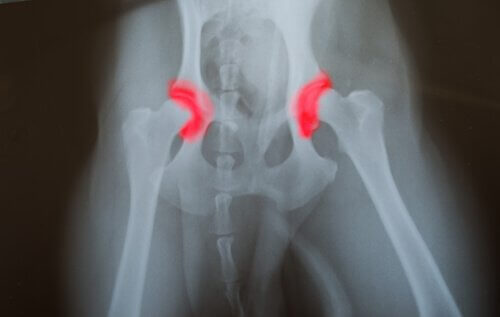

Als een puppy overvoed is zal hij in gewicht aankomen en als gevolg hiervan sneller groeien dan goed voor hem is. Dit zal zijn skelet teveel belasten en kan tot de volgende aandoeningen leiden:

- Osteochondrose

- Heupdysplasie

- Fragmentatie en fissuur (kleine breuk) van het coronoïde proces

In 1974 analyseerde een studie 12 paar Deense doggen die een dieet volgden met een hoog gehalte aan eiwitten, fosfor en calorieën. De eerder genoemde ziekten kwamen vaker voor bij de honden die deze voedingspatronen volgden.

Bij volwassen honden veroorzaakt overvoeding een reeks van verschillende gezondheidsproblemen. De slijtage van de gewrichten lijkt bij oudere honden één van de meestvoorkomende symptomen te zijn.